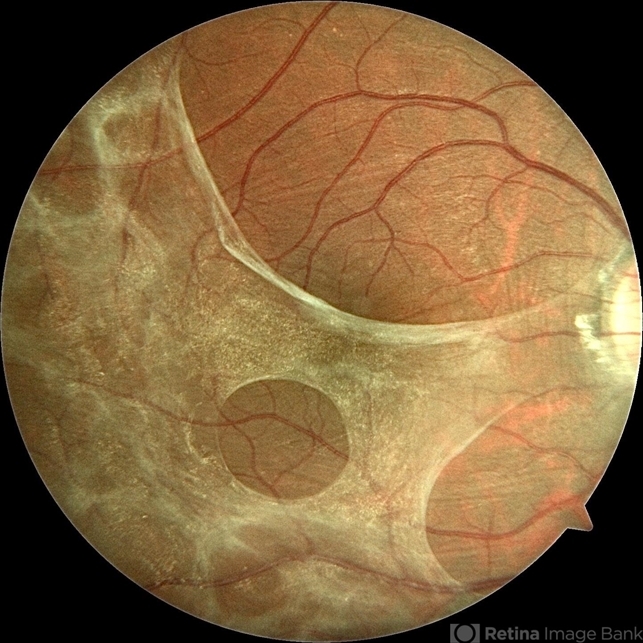

- fundus photograph, thickening of the posterior hyaloid, ocular toxoplasmosis, epiretinal membrane (ERM)

- Color fundus photograph of the right eye of a 36-year-old man showing thickening of the posterior hyaloid associated with an epiretinal membrane due to ocular toxoplasmosis.